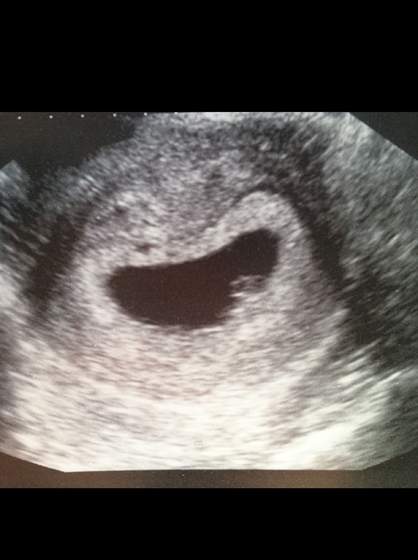

Ja po pierwszym usg :) wszystko pieknie, Fasolinka ma 7mm czyli odpowiada dokladnie moim 6tyg 3d :D

Widzielismy tez na ekranie pulsujace serduszko :)

Najpierw mialam robione usg przez brzuch, i pani juz mowila, ze chyba widzi serduszko, ale jeszcze zrobila mi dopochwowe, zeby sie upewnic i stwierdzila, ze wszystko jak na ten wiek ciazy wyglada perfekcyjnie, zarodek osadzony w prawidlowym miejscu, prawidlowy rozmiar, pulsujace serduszko

a oto Ktosiek: